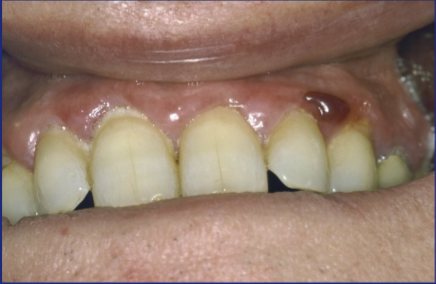

Drug induced gingival hyperplasia

What is this?